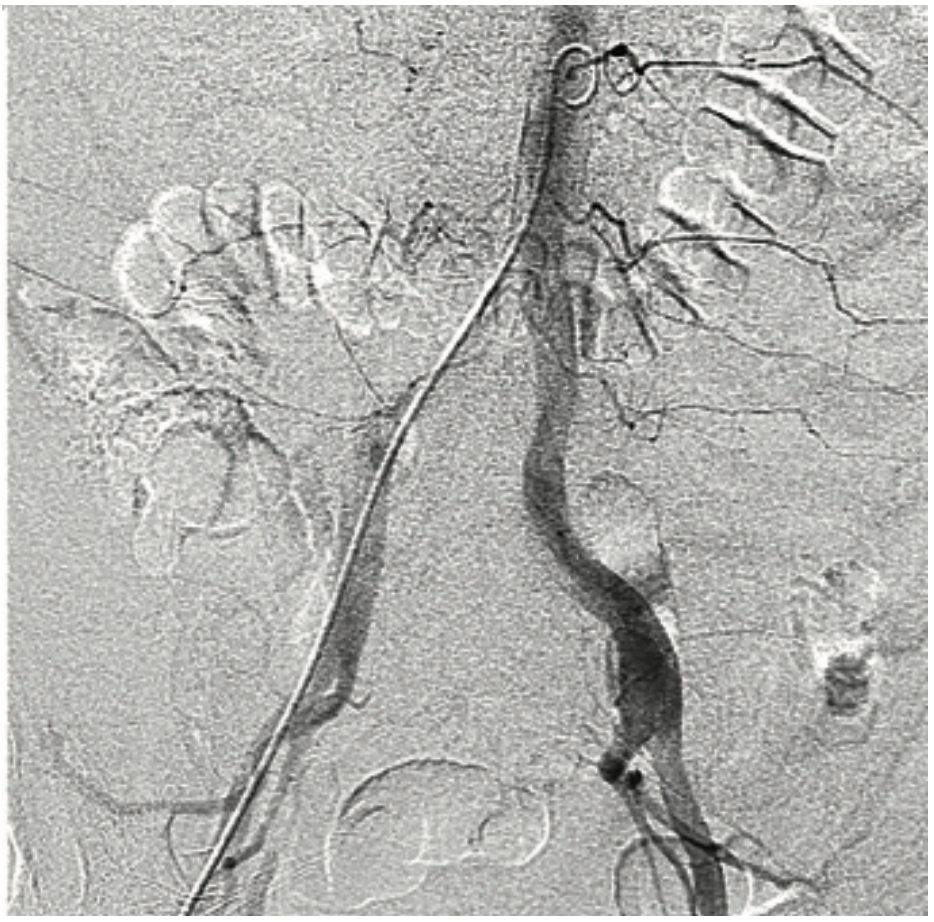

For mitral valve procedures, we use the ACIST to determine the mitral annular plane. It definitely requires high-flow injections, because there is a lot of volume going through the mitral valve. You also have to switch from doing a left atrial angiogram, which requires maybe 10 ccs of contrast, to doing a left ventriculogram, which requires maybe 10-20 ccs of contrast. The ACIST permits us to move between those injections quickly. If you are trying to characterize the left or right atrium in a transseptal procedure, it can easily be done with the ACIST. Another advantage of the ACIST is that because it offers higher and more consistent flow than with a hand injection, I can keep my small catheter in place and still get an optimal result. We also use the ACIST for left atrial appendage closures (Image 1). Using pre-procedural CT scans, the Philips system allows you to overlay your CT images onto the fluoroscopic image. Using an ACIST contrast injection hooked up to the Philips system, you can also do a rotational angiogram to generate a 3D image. We have also used the ACIST for pulmonary angiograms (Images 2-3) and pulmonary stenting. The images show a case of a patient who presented with acute chest pain. We were able to image his coronaries and when these proved to be normal, we performed a pulmonary angiogram in the same setting. For pulmonary valve stenting, you definitely need a contrast injection in the right ventricular outflow tract to make sure you have the necessary size and space. If you do a coarct stent as well, you want a high-flow injection to characterize the anatomy. I was involved in stem cell studies a few years ago, and in determining the sites for injection, we would perform a left ventriculogram to characterize where we want to inject cells, and quickly move to a coronary injection to guide our injections, without having to change the system between angiograms.

This is a 79-year-old woman with emphysema, arthritis, and severe aortic stenosis, and she needed a TAVR. There were several issues with her TAVR: one was that her coronary heights were low. If you put a TAVR valve in a patient with very low coronary heights, there is a chance that the native valve will get pushed up and occlude the coronary artery. We’ve had that happen once before, and the patient died from it, so it is a very serious complication. We did a novel procedure called the bioprosthetic aortic scallop intentional laceration to prevent iatrogenic coronary artery obstruction (BASILICA) procedure, where you slice the leaflet of the native aortic valve in half. Even though the leaflet gets pushed up, since it has been sliced in half, it won’t occlude the coronary artery. We first needed to look at her coronary arteries and the cusps using 3-6 cc coronary injections, and then we performed the BASILICA procedure. The patient also had an anomalous takeoff of her carotid arteries. We wanted to use a carotid embolic protection device, but because she had such an anomalous takeoff, it had to be placed in a very unique way. We did have a CT scan and had to correlate it with the patient so we would know exactly where to put the device. We needed to take an arch angiogram, which is a higher power contrast injection, 10 for 15 ccs or 10 for 20 ccs. The TAVR procedure was done as usual, using the 10 cc contrast injection I described earlier, to measure the annulus planes and look at implant depth. Then we looked at the coronary arteries, because it turned out that the patient needed a stent in her coronary artery. At the end of the case, we wanted to make sure that our closure of the large-bore access sheath was sufficient, so we flipped down to the leg and took a picture there using digital subtraction angiography and a 2 cc injection. I’ll share a second case that also demonstrates the versatility of the ACIST (Images 2-6). This was a patient with acute shortness of breath and chest pain, and there was a question of whether he was having a pulmonary embolus or a heart attack. The electrocardiogram was unclear. We took him back to the lab and were able to do a pulmonary angiogram, then visualize the coronaries, all on one setting. We also did an iliac angiogram, because we used that access in order to give him a support device. This case required pulmonary (Images 2-3), coronary (Images 4-5), and iliac angiograms (Image 6), all done with use of the ACIST CVi system.